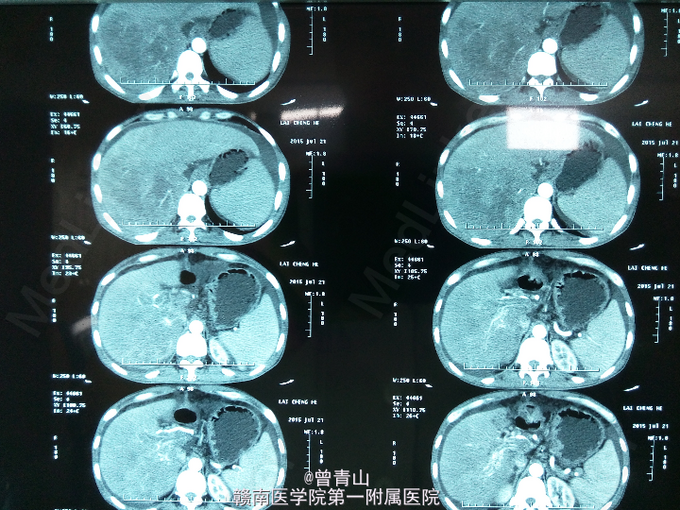

查体:腹部稍膨隆,硬,全腹可及轻度压痛及反跳痛,肝肋下右锁骨中线处4cm处可触及,脾脏未触及,肝区叩击痛阳性,移动性浊音阳性,肠鸣音弱,未见肝掌及蜘蛛痣。辅助检查:血分析:红细胞(仪器法)3.99*10^12/L,中性细胞比率85.91。甲胎蛋白(化学发光)104517ng/ml。凝血功能:(AT3)AT-Ⅲ51.3%,凝血酶原时间14.2s,D-二聚体4.84mg/L。尿分析:蛋白质1+,酮体1+,白细胞55.6/ul,管型20.81/ul,浊度1+。大便常规正常。肝功能:天门冬氨酸氨基转移酶(速率法)47U/L,总蛋白(双缩脲法)55.8g/L,白蛋白(溴甲酚绿法)30.3g/L,总胆红素(酶法)22.9umol/L,直接胆红素12.6umol/L。乙肝表面抗原>>225.000ng/ml,乙肝核心抗体>>4.020PEIU/ml。上腹部增强CT提示:肝增大,肝右叶见10.0*12.5cm大小低密度肿块,增强扫描早期呈不均匀强化,门静脉期与延迟期呈低密度,门静脉主干与左右分支内见低密度充盈缺损,门静脉周围见多发性迂曲血管影。

患者目前诊断:肝右叶原发性肝细胞肝癌并门静脉癌栓形成。处理:给予护肝、补液、营养支持等对症处理。由于患者肝癌并门静脉癌栓形成,一般情况较差,在我院的技术尚不能给患者行手术治疗,也无其余更好的治疗方法,建议去肝胆外科知名度高的医院就诊。